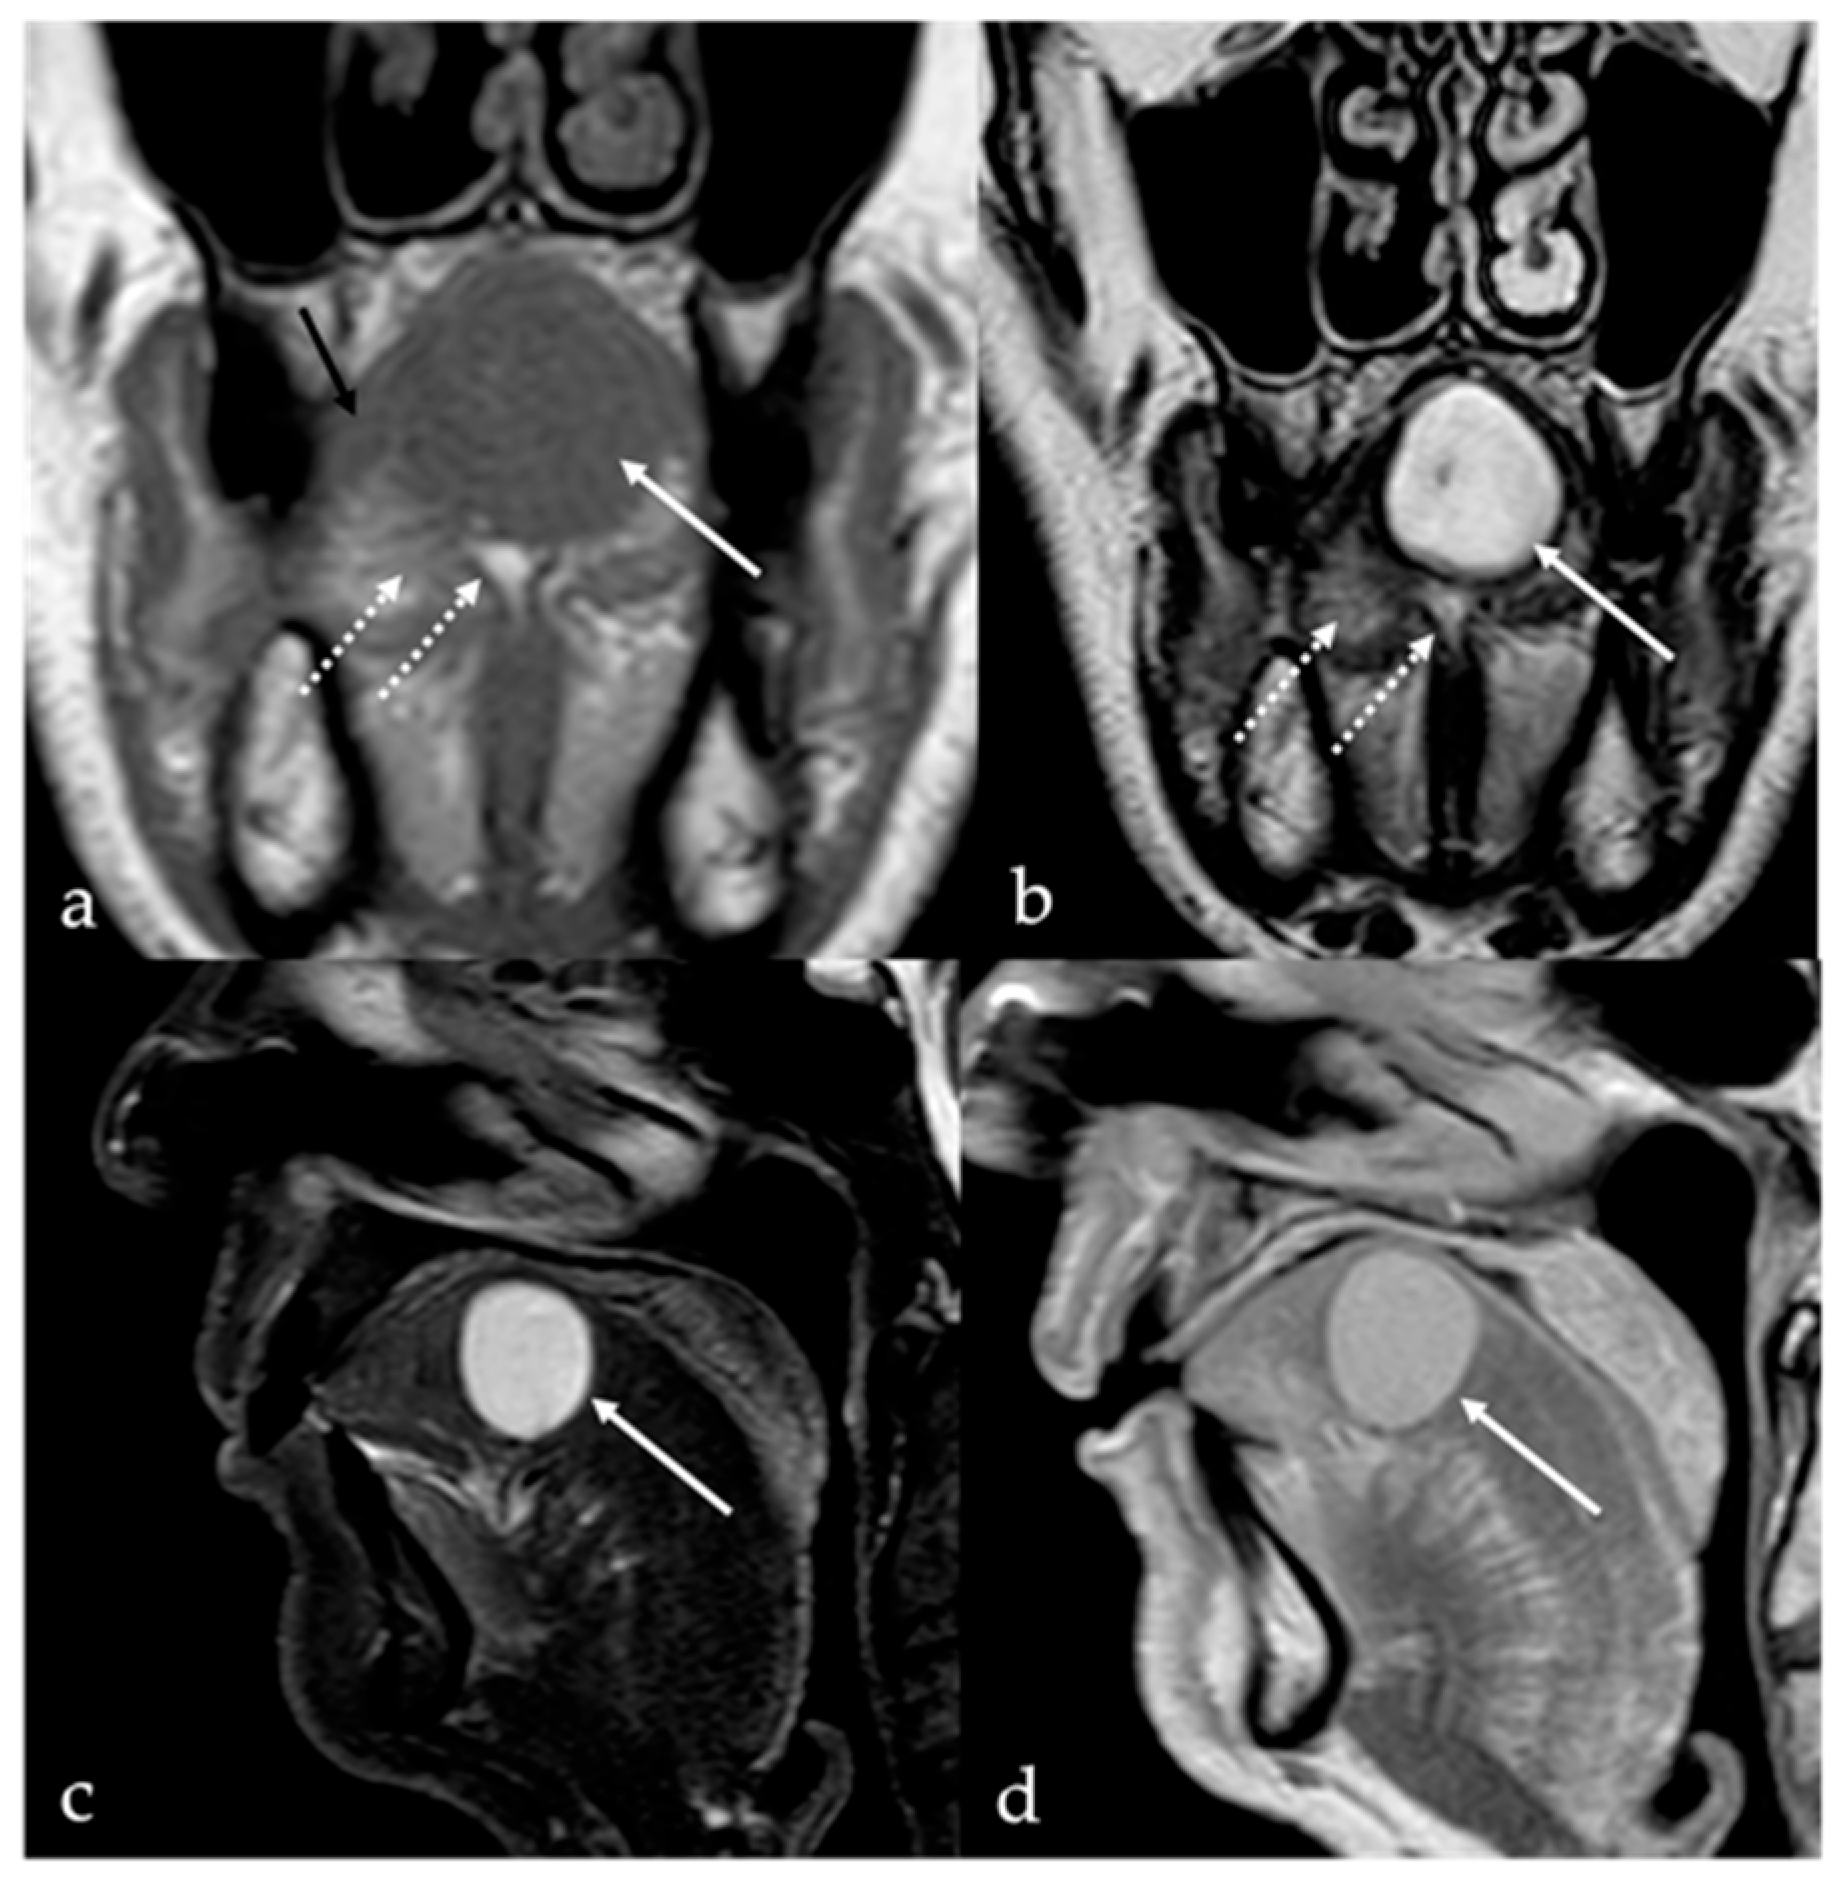

5.1. Venous Malformations

| Venous malformation [1,9] | CT: phleboliths MRI: high T2 SI, +CE | Other vascular malformations, schwannoma, dermoid cysts |